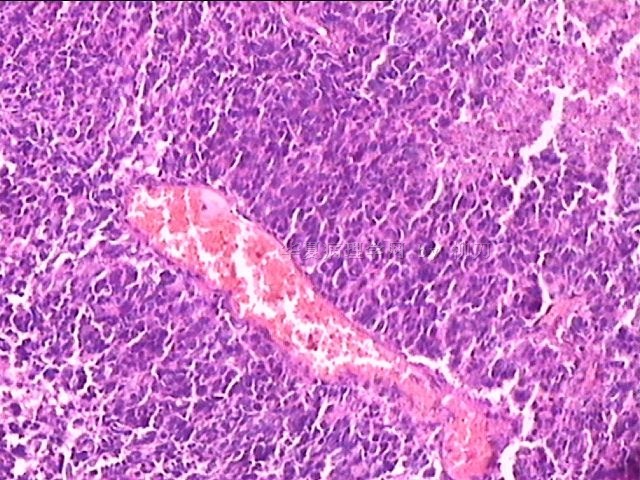

女,34y,头痛一月,右额叶占位:5*5*4cm。囊性区域,4cm。大体:3.5x3x1cm灰白间暗褐色组织一堆,质嫩。临床诊断1:胶质瘤,2:血管母细胞瘤。

• 额叶占位,胶母典型不?图1

图1

胶母

同意胶质母细胞瘤。细胞异型、坏死、核分裂、血管内皮肿胀增生均可见到。

This is certainly a WHO grade IV malignant neoplasm. While most likely a glioblastoma, I would carefully rule out PNET by staining for GFAP and neuronal markers such as synaptophysin, NeuN and NSE. Rarely, PNET may shows marked pleomorphism and indistinguishable from glioblastoma on HE stain.

同意马老师的意见,该肿瘤从形态及年龄来看考虑PNET或GBM,须标记Syn、NSE、S-100、NeuN和GFAP来鉴别。

结合图片细胞形态特点考虑胶质母细胞瘤,组化标记排除其他